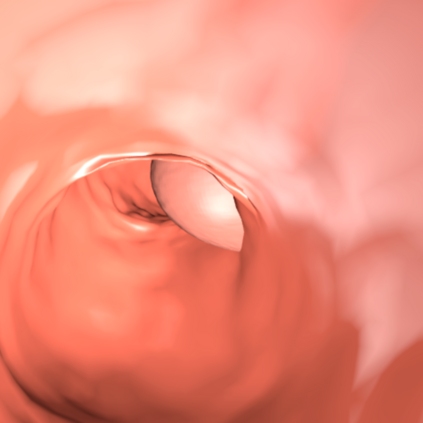

Deep learning has shown excellent performance in analysing medical images. However, datasets are difficult to obtain due privacy issues, standardization problems, and lack of annotations. We address these problems by producing realistic synthetic images using a combination of 3D technologies and generative adversarial networks. We use zero annotations from medical professionals in our pipeline. Our fully unsupervised method achieves promising results on five real polyp segmentation datasets. As a part of this study we release Synth-Colon, an entirely synthetic dataset that includes 20000 realistic colon images and additional details about depth and 3D geometry: https://enric1994.github.io/synth-colon